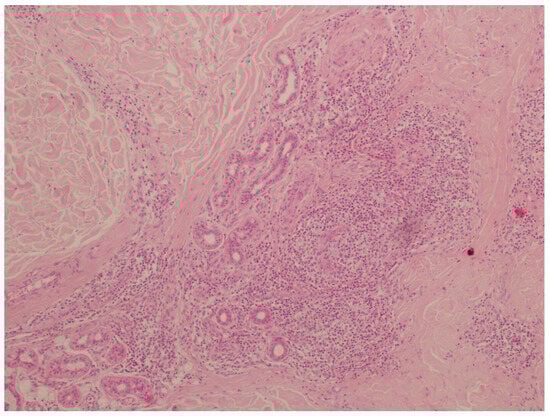

2. Case Presentation